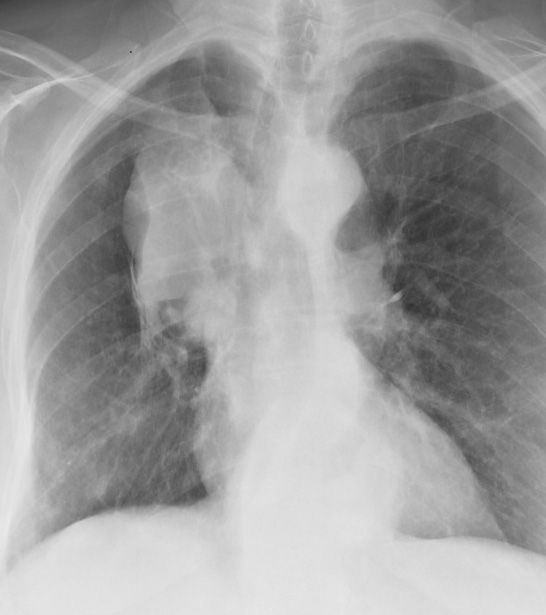

Gallery Lobar Collapse RUL Collapse RUL Collapse Case 2 PA (no lateral)

RUL Collapse Case 2 PA (no lateral)